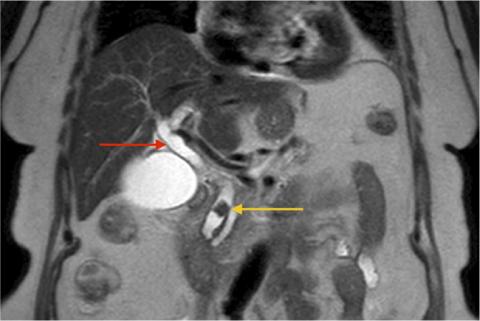

MR-kolangiopankreatografi, som viser tydeligt dilateret ductus choledochus (rød pil) med fyldningsdefekt distalt på baggrund af en konkrement (gul pil).